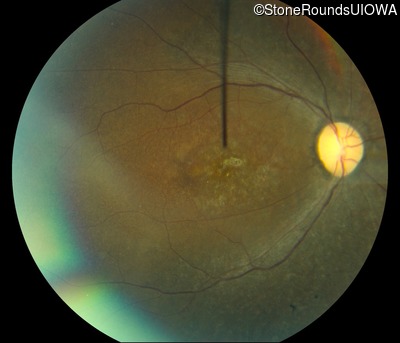

Fundus Photography - Right - 20/1000 sc

Exemplar

Fundus Photography - Left - 20/500 sc